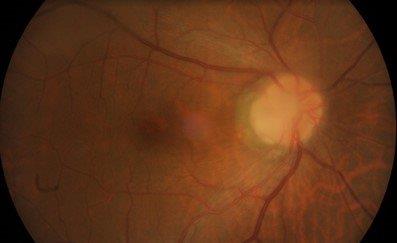

A 58-year-old male with no underlying medical history was referred for retinal oedema adjacent to the optic nerve head with cystic changes and a shiny appearance on the overlying retina for the right eye. Unaided visual acuity was 6/9 and 6/6. He was asymptomatic and was incidentally noted to have macula oedema during a routine examination. The anterior segment examination was normal, but the right eye optic disc assessment showed a greyish-white depressed area in the temporal quadrant (Figs 1 and 2) along with cystic changes at the macula. The left eye examination was normal. OCT examination of the right eye showed schisis-like separation of retinal layers, most marked in the outer retinal layers, extending up to the optic disc temporal margins (Fig 3). There appeared to be a clear communication between the optic disc and the schisis-like separation of outer retinal layers.

Fig 2. Fundus photograph of patient’s right optic disc pit with subtle-appearing maculopathy with a small amount of

reduced definition of the background choroidal vessels near the papillomacular area

Clinically, ODP usually appears as a greyish-whitish, round or oval depression of the optic disc (Fig 1), and it may have different levels of severity. More than half of the patients in their third or fourth decade go on to develop maculopathy. Typically, OCT demonstrates fluid in the sub-retinal and intra-retinal compartments. The outer retinal layers are more commonly affected and the OCT demonstrates schisis-like separation of the outer retinal layers. Very often, schisis-like separation of the retinal layers extends to the optic disc pit, as seen in this case.